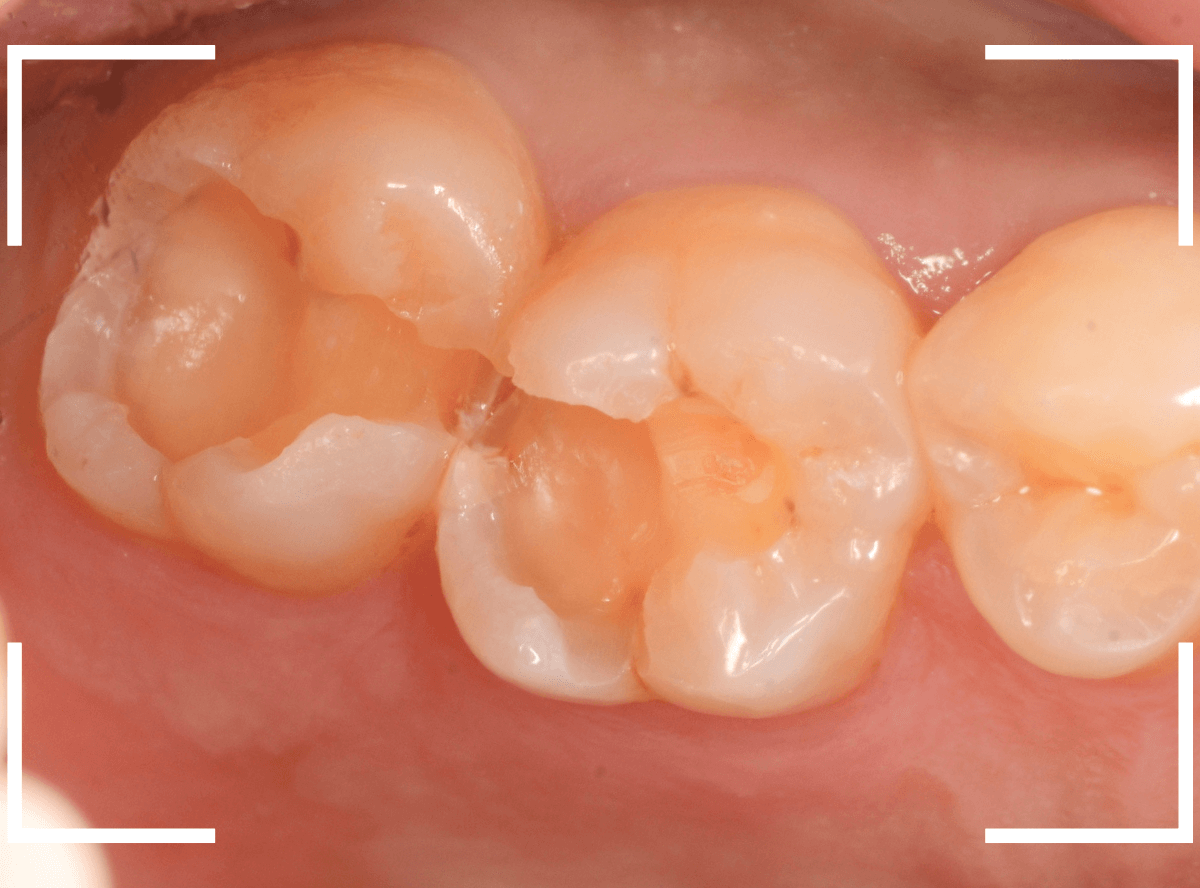

Case.8 治療を中断して、つめものが取れてさらに虫歯が進行したケース

こちらも、前のケースの方と同じように、治療中断後、つめものが取れて長期間放置してしまった患者さんのケースです。

しみるなどの症状が現れたので、来院に至ったようなのですが、症状が出ている場合、だいたい、虫歯は重症化している事が多いです。

レントゲン写真で確認します。

青いラインが神経、赤いラインが虫歯と思われる部分です。

前後の歯まで、虫歯が広く進行しているのが想定できます。

虫歯の治療を開始すると、すぐに深めの虫歯が出てきました。

神経に近い部分まで虫歯が進行していますので、慎重に虫歯を除去します。

全ての虫歯を除去しました。

前後の歯にまで虫歯が広く進行していました。

場合によってはお痛みが出る可能性をお話しし、お薬をつめて経過観察をしました。

いつものフレーズになりますが、症状が出てからの歯科受診は、このように大きく歯を削る治療になります。また、手遅れになっている事も多いです。

お口の中のトラブルの多くは定期的なメンテナンスによって、防ぐことができます。

ご自身の身体のことですので、将来後悔のないようにしてください。